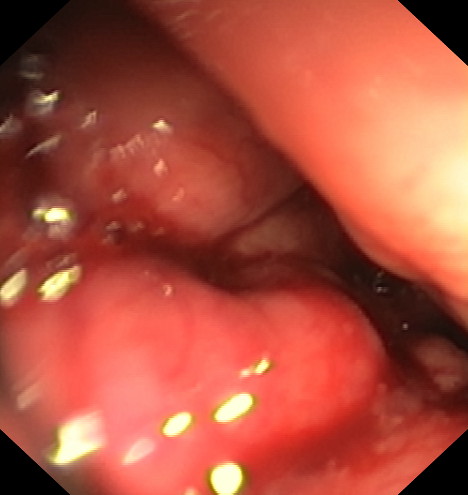

Mediante un sistema de sutura acoplado a un endoscopio, se sutura el estómago “desde dentro” dándole un aspecto similar al conseguido por la cirugía de gastrectomía vertical laparoscópica (manga gástrica quirúrgica), pero con menor riesgo quirúrgico y muy buenos resultados a medio y largo plazo. De esta manera se limita la cantidad de comida que puede entrar en el estómago e igualmente hace que la digestión sea más lenta, favoreciendo enormemente la saciedad y la pérdida de peso. Es una técnica definitiva, pero por vía oral, ni realizar heridas abdominales ni cicatrices.